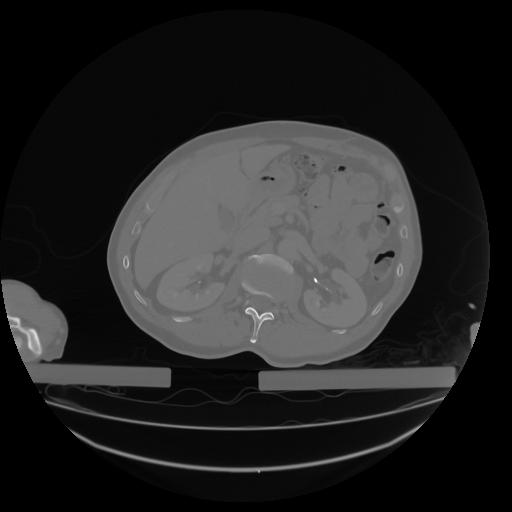

27 CUERPO,CE,Axial,3.0,CUERPO,,